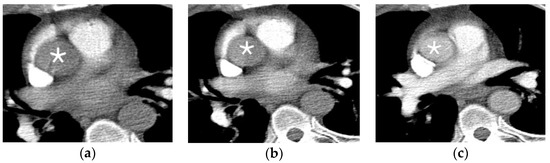

2.4.1. Active Arterial Extravasation